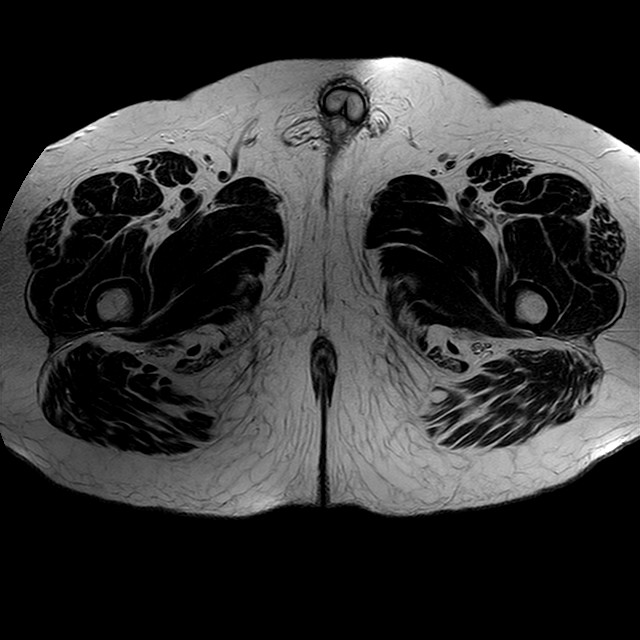

Esami: RMN BACINO

eT2w TSE

Evidenti e simmetriche alterazioni osteofitosiche in regione coxo femorale con riduzione delle rime articolari. Degenerazione completa del cercine glenoideo. Non attuali segni di versamento articolare. Non segni di edema osseo che escludono attuale algodistrofia od osteonecrosi. Lieve e simmetrica riduzione del trofismo della muscolatura glutea.